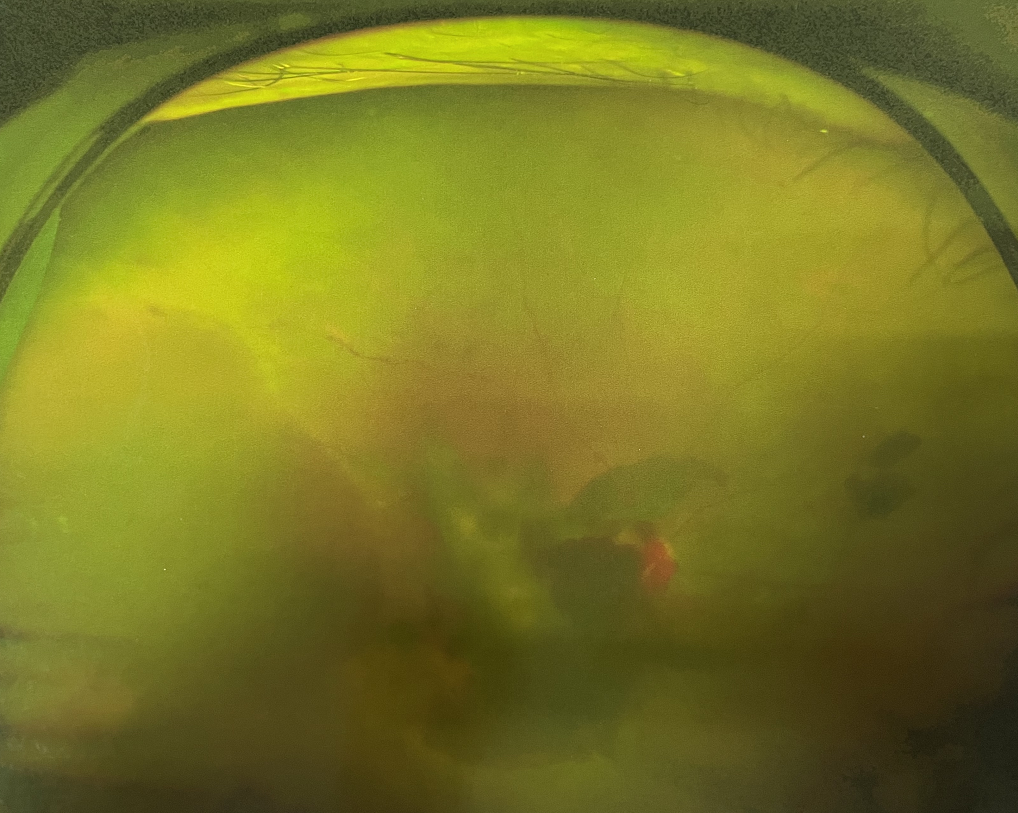

眼底出血多指玻璃體內(nèi),眼睛更深處的視網(wǎng)膜出血。通常情況下,肉眼難以發(fā)現(xiàn)眼底出血,而且發(fā)病初期眼睛也無明顯癥狀,只有借助專業(yè)的眼底檢查儀器才能觀察到異樣。那么眼底出血嚴(yán)重嗎?

眼底出血嚴(yán)重嗎?對(duì)于已出現(xiàn)黃斑水腫、視網(wǎng)膜新生血管的患者,根據(jù)眼底血管造影、oct等檢查結(jié)果,給予玻璃體腔注射抗VEGF藥物及激光治療,可以減輕黃斑水腫,使視網(wǎng)膜新生血管消退,以免進(jìn)一步發(fā)生玻璃體出血、視網(wǎng)膜脫離等嚴(yán)重并發(fā)癥的出現(xiàn)。對(duì)于玻璃體出血者,傳統(tǒng)認(rèn)為玻璃體出血3-6個(gè)月不吸收再進(jìn)行手術(shù)干預(yù),但近年來因?yàn)轱@微手術(shù)設(shè)備及玻璃體切割技術(shù)已非常成熟,故對(duì)于1個(gè)月不吸收的玻璃體出血者就可以考慮手術(shù),即手術(shù)時(shí)機(jī)應(yīng)該具體情況具體分析,因人而異。